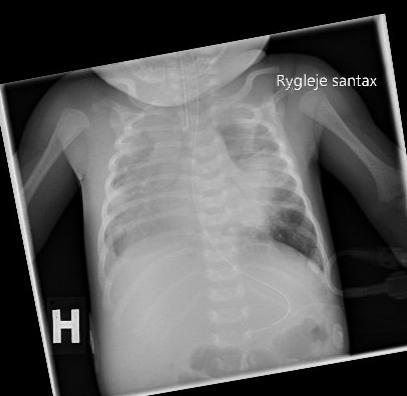

Røntgenbillede af thorax taget et døgn inden udskiftnings­transfusion. Der ses infiltrative og atelektatiske forandringer i begge lunger samt små væskeansamlinger i begge pleurae.

En tre uger gammel pige blev indlagt på et lokalsygehus efter et døgn med hoste, respirationsbesvær og cyanosetilfælde. Hun blev lagt i nasal continuous positive airway pressure (n-CPAP). En røntgenundersøgelse af thorax viste bilaterale infiltrater, og der blev påbegyndt behandling mod pneumoni. I en svælgpodning fandt man dagen efter B. pertussis-DNA ved polymerasekædereaktion (PCR), og der blev påbegyndt behandling med clarithromycin. Trods antibiotikabehandling og respirationsstøtte i form af n-CPAP måtte pigen overflyttes til et neonatalt intensivafsnit i respirator.